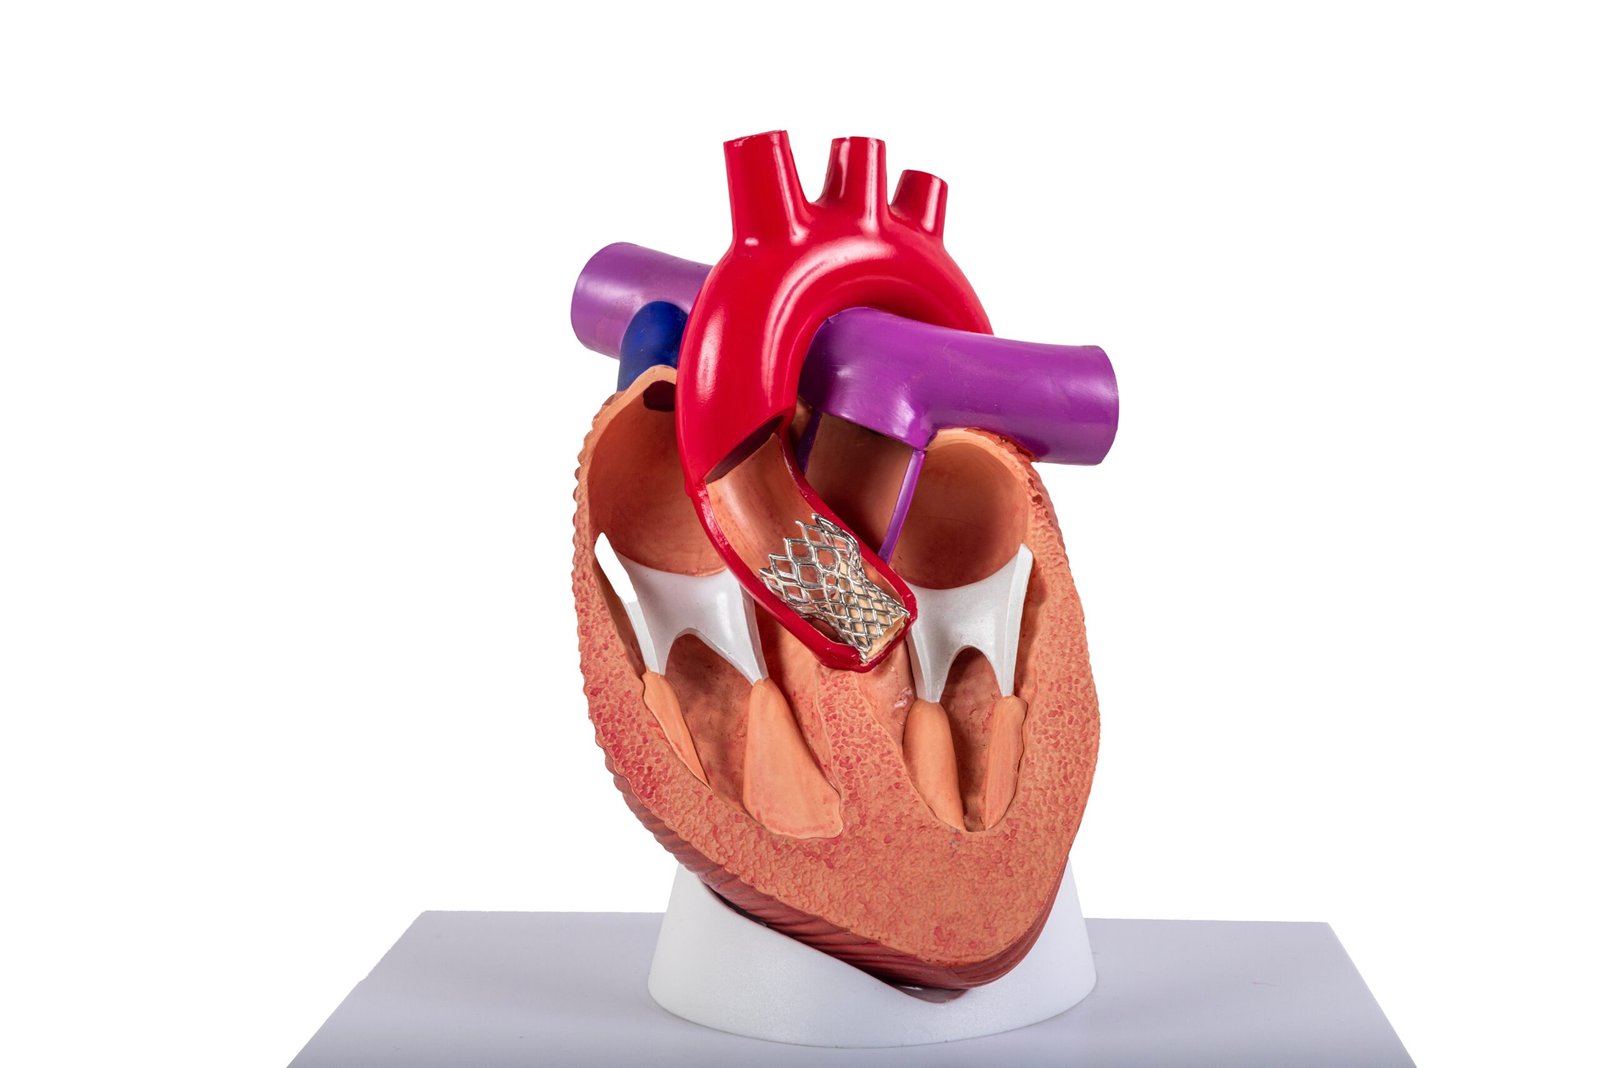

Minimally Invasive, Maximum Impact: The Benefits of Transcatheter Aortic Valve Implantation (TAVI)

Transcatheter Aortic Valve Implantation (TAVI) is transforming heart care for patients with aortic s…